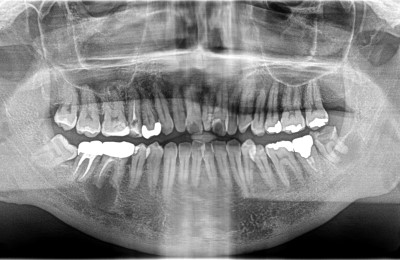

CASE02精密根管治療

Before

After

| 主訴 | 左右の奥歯の歯茎が腫れた。 |

|---|---|

| 治療方法 | 右下6番目、左下8番目の歯に大きな根尖病変(膿の袋)が認められる。また、右上6番目にも根尖病変、右上5番目に不良な根管充填が認められる。 ラバーダム防湿および拡大視野下にてそれぞれ精密根管治療を行った。 |

| 治療期間 | 約6ヶ月 (1歯あたり2~3回。治療後の経過観察期間も含める。) |

| リスク | 治療後、病変が再発したり治癒しなかった場合は外科処置が必要となる場合がある。 歯根破折が認められた場合は抜歯適応となる。 |

| 費用 | 110,000円(小臼歯)×1 132,000円(大臼歯)×3 ※被せ物の料金は別途88,000円×本数かかります。 |